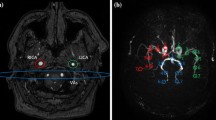

RICA and LICA indicate the label images of the right and left carotid artery, respectively, and BA indicates the basilar artery. A schematic of the RICA calculation is presented in Fig. 1. In the flow territories of contralateral arteries, the calculation leads to a negative signal. These voxels are set to zero.

Calculations of the final images for the example of the right internal carotid artery. (a) Self-controlled super-selective ASL. (b) Conventional super-selective ASL. In both examples, the right internal carotid artery is visualised. The subscript “L” indicates label images and “C” control images, while “final” indicates the final calculated images. Note that black numbers represent blood signal and red numbers static tissue signal. In (a), all negative signal in the flow territories of the contralateral arteries (in this example LICA and BA) of the final image is artificially set to zero after the calculations (not shown)

The data acquired for this study were part of a general protocol for MRI pulse-sequence development approved by the local ethical committee. Volunteers gave written informed consent. The study population included six healthy volunteers (4 women and 2 men, mean age 24.8 years) with no known history of intracerebral pathologies. All experiments were performed on a Philips 3T Achieva MR scanner (Philips Healthcare, Best, The Netherlands) using a standard 32-channel head coil. For planning of selective ASL, the information regarding the position of the arteries was obtained via time-of-flight angiography [12].

The tagging and readout parameters were kept identical between the selective and non-selective approaches. The labelling duration was 1650 ms, and the post-labelling delay was 1600 ms. For selective labelling of the ICA and the BA, the additional gradient moments were 1.08 mT/m in Gx and Gy directions [16]. With the self-controlled approach, the labelling spot changes its position after each acquisition. These positions of the arteries of interest were chosen manually. The spot then “cycles” from the right ICA to the left ICA, then to the BA. This is repeated until all scan acquisitions (label images in self-controlled ss-ASL) are completed. Images of all three flow territories can thus be retrieved from a single scan [12]. Image acquisition was performed as single-shot multislice echo planar imaging (EPI) with 2.75×2.75 mm2 in-plane resolution and 16 slices with 5-mm thickness covering 95 mm. The following parameters were used: field of view, 240×240 mm; TR/TE, 3847/13 ms; flip angle, 90°. In non-selective ASL, 40 acquisitions were performed (20 label/control pairs); for super-selective ASL, a total of 120 acquisitions were performed (20 label/control pairs for each artery); and for self-controlled ASL, 60 acquisitions (20 label images for each artery). Scan time was 14:36 min using super-selective ASL, 7:18 min with self-controlled ASL, and 4:52 min for non-selective ASL.

Image acquisition was performed successfully in all volunteers, and no data sets had to be discarded due to movement or misplaced labelling foci. Figure 2 shows representative images of both quantitative CBF images of all flow territories (a) and relative CBF images of the RICA and a difference image of both (b). The difference image was created by subtracting the conventional image from the self-controlled ss-ASL. This image shows the difference in signal in the peripheral grey matter zones that is mostly image noise, indicating no major differences between the two methods (red arrows).

(a) Representative images of one volunteer after quantification of CBF data. In the upper row, non-selective and conventional super-selective ASL images are presented. The bottom row shows self-controlled super-selective ASL images. Both the selectivity and the quantitative values appear similar in all approaches (b) Relative CBF (rCBF) images of the RICA showing the gain in SNR of self-controlled ss-ASL compared to the conventional approach, and a difference image of both approaches. The difference image shows differences in signal, which can be largely attributed to noise, indicating no significant differences between methods (red arrows)